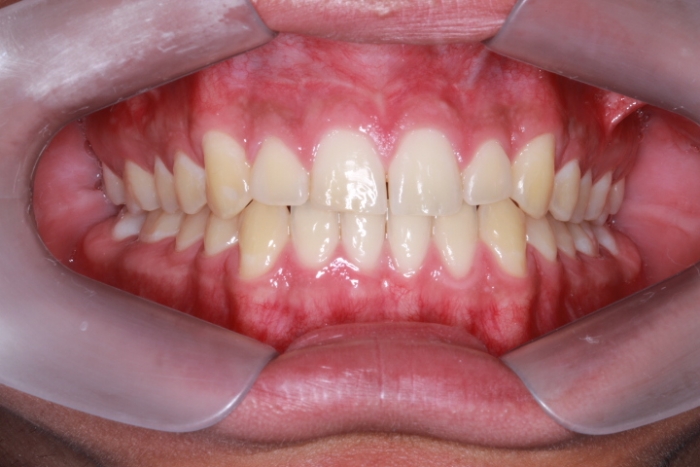

Intra oral - Caninos em posição - Clínica Cliniface

Intra oral - Caninos em posição

Intra oral com tratamento ortodôntico finalizado 03/16 - Clínica Cliniface

Intra oral com tratamento ortodôntico finalizado 03/16